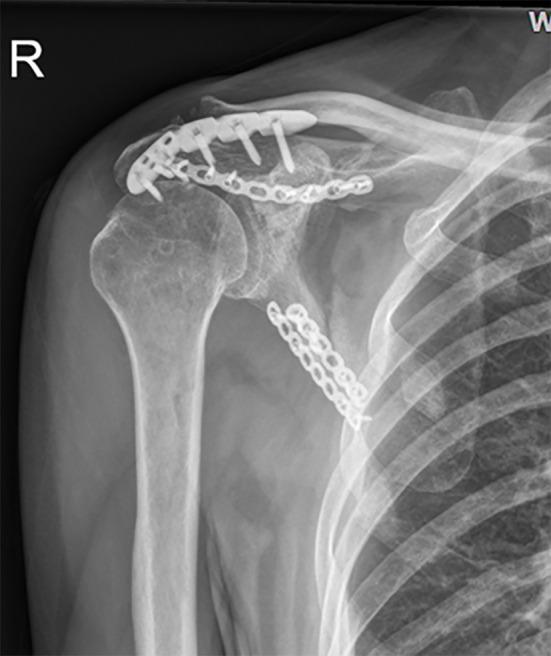

A 62-year-old man was admitted to our emergency department 6 h after his right shoulder and back were impacted by heavy objects. The patient presented chest tightness and shortness of breath. Chest computed tomography (CT) showed pneumohemothorax, multiple rib fractures, and right scapula fractures. Three-dimensional CT reconstruction of the right shoulder joint showed a trans-spinous scapular neck fracture with a glenohumeral joint dislocation. Rotator cuff injury was suspected because the patient had a glenohumeral joint dislocation and was then confirmed by shoulder magnetic resonance imaging. A staged surgery was performed, including open reduction and internal fixation of the right scapula fracture and repairing of rotator cuff by right shoulder arthroscopy. At the 5-mo follow-up, the fracture line was blurred and the shoulder joint function was good.

Fracture of the scapular neck combined with rotator cuff tear is rare and the rotator cuff injury should not be ignored in clinical work. Stable internal fixation combined with secondary arthroscopic repair of rotator cuff tear can achieve good results.